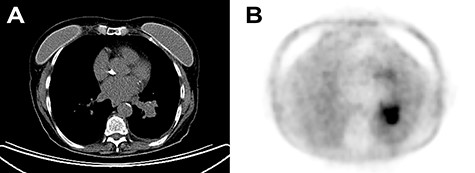

A 72-year-old Italian woman came for persistent non-productive cough since late 2017. Chest X-ray showed leftvbasilar atelectasia. Previous history of smoking, hypothyroidism, osteoporosis and gastroesophageal reflux disease was noted. A chest computed tomography (CT) displayed subcentimetric cavitated nodules and a 38-mm solid lung mass (Fig. 1a). Enlarged lymph nodes were present in the left hilar region.

(A) Chest CT with contrast enhancement displaying a solid lung mass of 38 mm characterized by polycyclic margins and dysmorphic calcification. (B) PET/CT with fluorodeoxyglucose revealing high glucose metabolism of the lung mass in the perihilar region of the left inferior lung lobe, near the left inferior lobar bronchus.

A positron emission tomography (PET)/CT revealed a lung mass near the left inferior lobar bronchus (Fig. 1b). There were no other pathologic enhancement on such examination. Scintigraphy excluded bone involvement. A bronchoscopy showed a whitish polilobular mass at emergence of left inferior lobe. Histology revealed neoplastic cells with solid growth pattern. Immunophenotype: CK7+, actin+, vimentin+, CK5/6+, TTF−, chromogranin−, CD56−, synaptophysin−, p63−, GFAP−, CEA−, ki67 15%. Malignant cells were found on the bronchoalveolar lavage. A neck and salivary gland ultrasound (US) excluded lesions to thyroid and to major salivary glands, along with absence of lateral cervical and submandibular pathological lymphadenopathy.